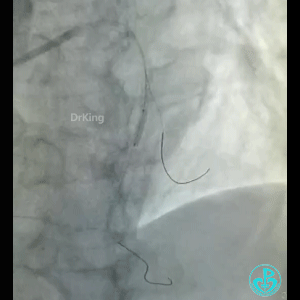

导丝怎么扩真怪!急性心梗前降支导丝通过顺利,球囊扩张后导丝移位很多!不在原来的血管腔!_https://www.jmylbn.com_新闻资讯_第2张

BMW导丝,预扩前导丝是弯曲的,预扩时球囊也是弯曲的,预扩后导丝拉直,血管的弯曲还在。

怎么解释导丝和血管的关系?